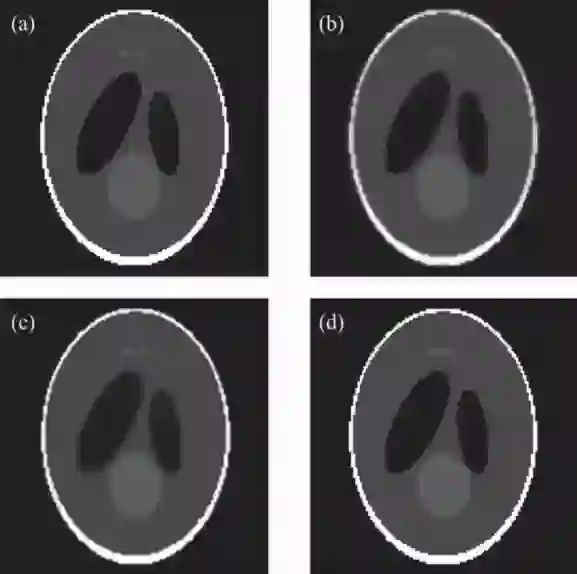

实验结果表明:与解析重建算法FDK相比,提出的算法在投影数较少的情况下,仍能获得较好的重建图像质量(见图1);与两种现有的基于TV正则化的迭代重建算法(ASD-POCS,EM-TV)相比,所提算法收敛速度提高6倍以上,且表现出更强的图像去噪和边缘保持能力(见图2)。此外,采用GPU加速手段使得上述迭代算法的重建时间大为减少(见表1)。

图2. 经典迭代算法与3DA-TVAL3算法的重建结果。(a)Sheep-Logan体模的原图像;(b)ASD-POCS算法的重建结果;(c)EM-TV算法的重建结果;(d)3DA-TVAL3算法的重建结果。